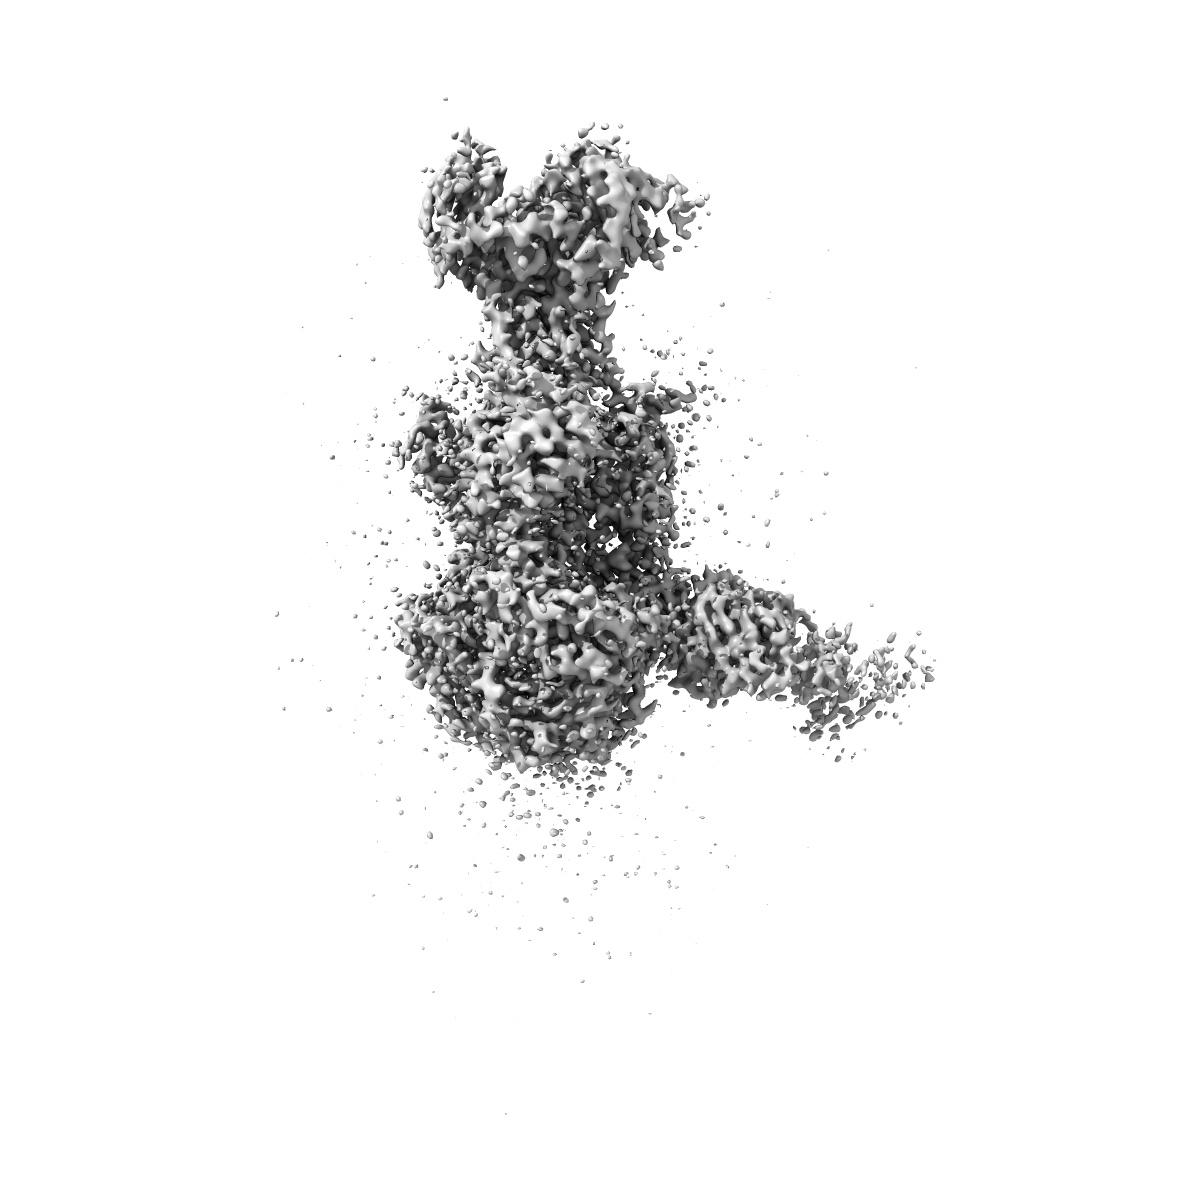

EMD-61612

Cryo-EM structure of VZV gB and FAB 16F9 complex

Single-particle3.12 Å

A broadly neutralizing antibody confers cross-genus protection against alphaherpesviruses by inhibiting gB-mediated membrane fusion.

(2025) Nat Commun , 16 , 11144 - 11144